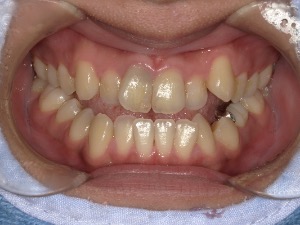

before

患者さんの年齢 30代 女性 症状 見た目がコンプレックス 治療内容 マウスピース矯正治療(抜歯あり) 費用 90万(税抜) 治療期間・回数 治療期間2年、通院回数10回 デメリット・リスク 期間がかかることがある 患者さまの声 なんでも噛める。本当に治療して良かった。 - 矯正治療